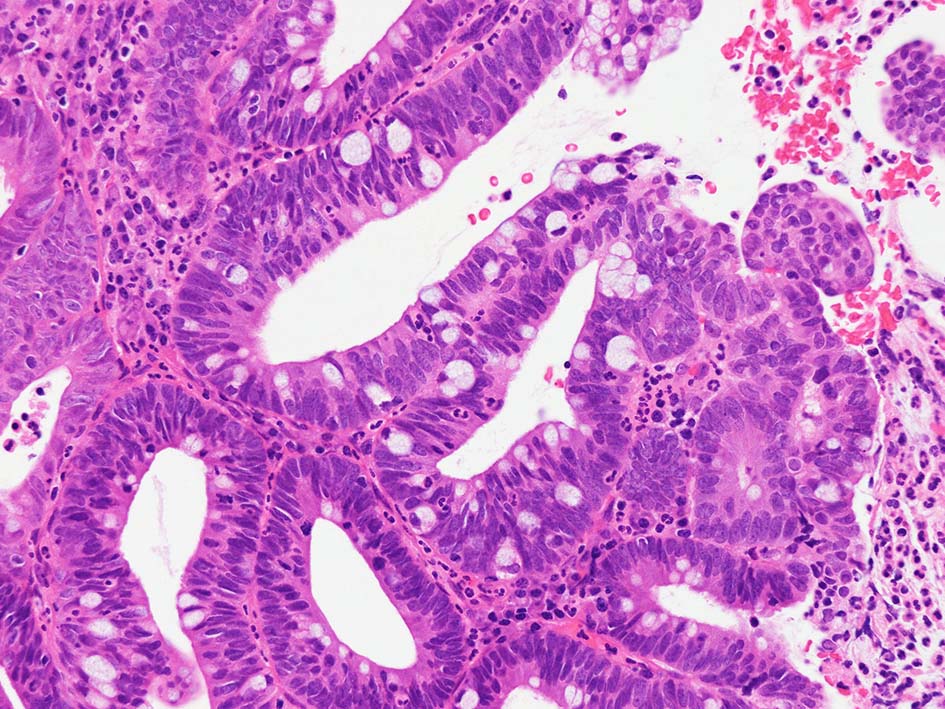

腸管型の腺癌。大腸の高分化腺癌と組織学的に区別は難しい.

desmoplastic fibrosis, 粘液浸潤のみられる組織片にはsig, porのadenocarcinoma浸潤が確認される.